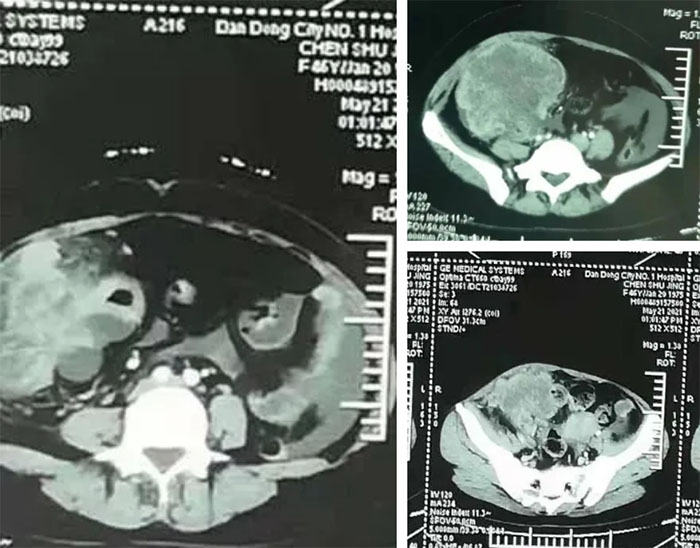

对此,丹东市第一医院普通外科吴瑶强副院长、妇产科尹庆云副院长、泌尿外科葛宏主任等医疗专家,成立MDT专家组,他们都拥有丰富的手术经验。不同学科的团队认真研究患者病历资料后认为,手术可以进行,在完成了严格术前准备后,以吴瑶强副院长带领的普外科团队为主,尹庆云副院长带领的妇科团队协助下,在泌尿外科,麻醉科,手术室等相关科室的密切配合下,手术有条不紊地进行。术中探查见肿物大小约16*12cm与周围侵犯明显,肠管因肿物压迫,明显扩张,腹腔空间狭小,手术难度巨大,经过坚持不懈的努力手术历时三个小时 ,肿瘤被满意切除,术中出血不到100ml。

肿瘤图片

肿物大小为16*12cm,重达5斤

术后病理回报:小肠恶性淋巴瘤